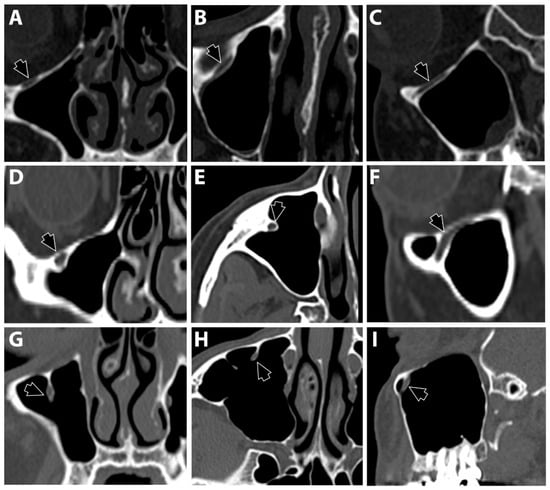

Three locations of the IOC were recorded following Ference et al. [14] and Haghnegahdar et al. [17]. Type 1 was recorded when the nerve canal was within the bone and outside the maxillary sinus lumen (Figure 2A–C). Type 2 was recorded when the nerve canal was within the roof of the sinus but slightly protruding from the lumen (Figure 2D–F). Type 3 was recorded when the nerve canal fully descended into the sinus lumen (Figure 2G–I).

Figure 2.

Three locations of the infraorbital canal (black arrows) following the classifications of Ference et al. and Haghnegahdar et al. [14,17] Type 1: the canal passes within the bony plate that forms the floor of the orbital cavity (A = coronal view, B = axial view, and C = sagittal view). Type 2: the bony canal protrudes into the lumen of the maxillary sinus (D = coronal view, E = axial view, and F = sagittal view). Type 3: the canal descends into the maxillary sinus (G = coronal view, H = axial view, and I = sagittal view).